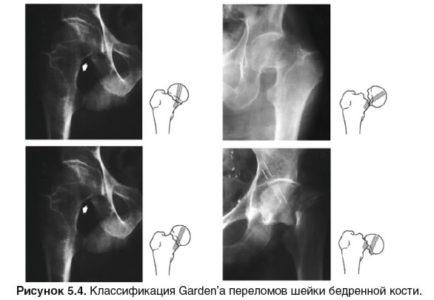

Далее представлена классификация и профилактика перелома шейки бедра.

Виды переломов:

- Чрезвертельный – повреждён участок костной ткани, соединяющий шейку бедра и его предвертельную часть, со значительной кровопотерей.

- Вколоченный – при смещении головки тазобедренной кости, её обломки не распадаются, а вколачиваются друг в друга.

- Оскольчатый – при данном переломе образуется более двух костных обломков.

- Открытый – сломанная кость пробивает кожные покровы.

- Закрытый – кожный покров не нарушен.

По анатомической локализации:

- Трансцервикальный – проходит прямо через шейку бедренной кости.

- Базисцервикальный – находится у основания шейки бедра.

- Субкапитальный – расположен очень близко к головке бедренной кости.

Часто задается вопрос, чем опасен трансцервикальный и базисцервикальный перелом шейки бедра? Второй, по сравнению с остальными видами, более благоприятен в прогнозе по дальнейшему сращению костей и не столь опасен, как другие.

Самый опасный вид перелома – субкапитальный, поскольку он сильно нарушает кровоснабжение головки. Ниже приложены фото компрессионного и базального перелома.

Также разделяют по углу линии перелома:

- 1-я степень – менее 30°.

- 2-я степень – от 30 до 50°.

- 3-я степень – более 50°.

Чем больше угол этой линии, тем выше шансы сильного смещения при переломе, из-за чего он либо срастётся с большими сложностями, либо не срастётся вообще.